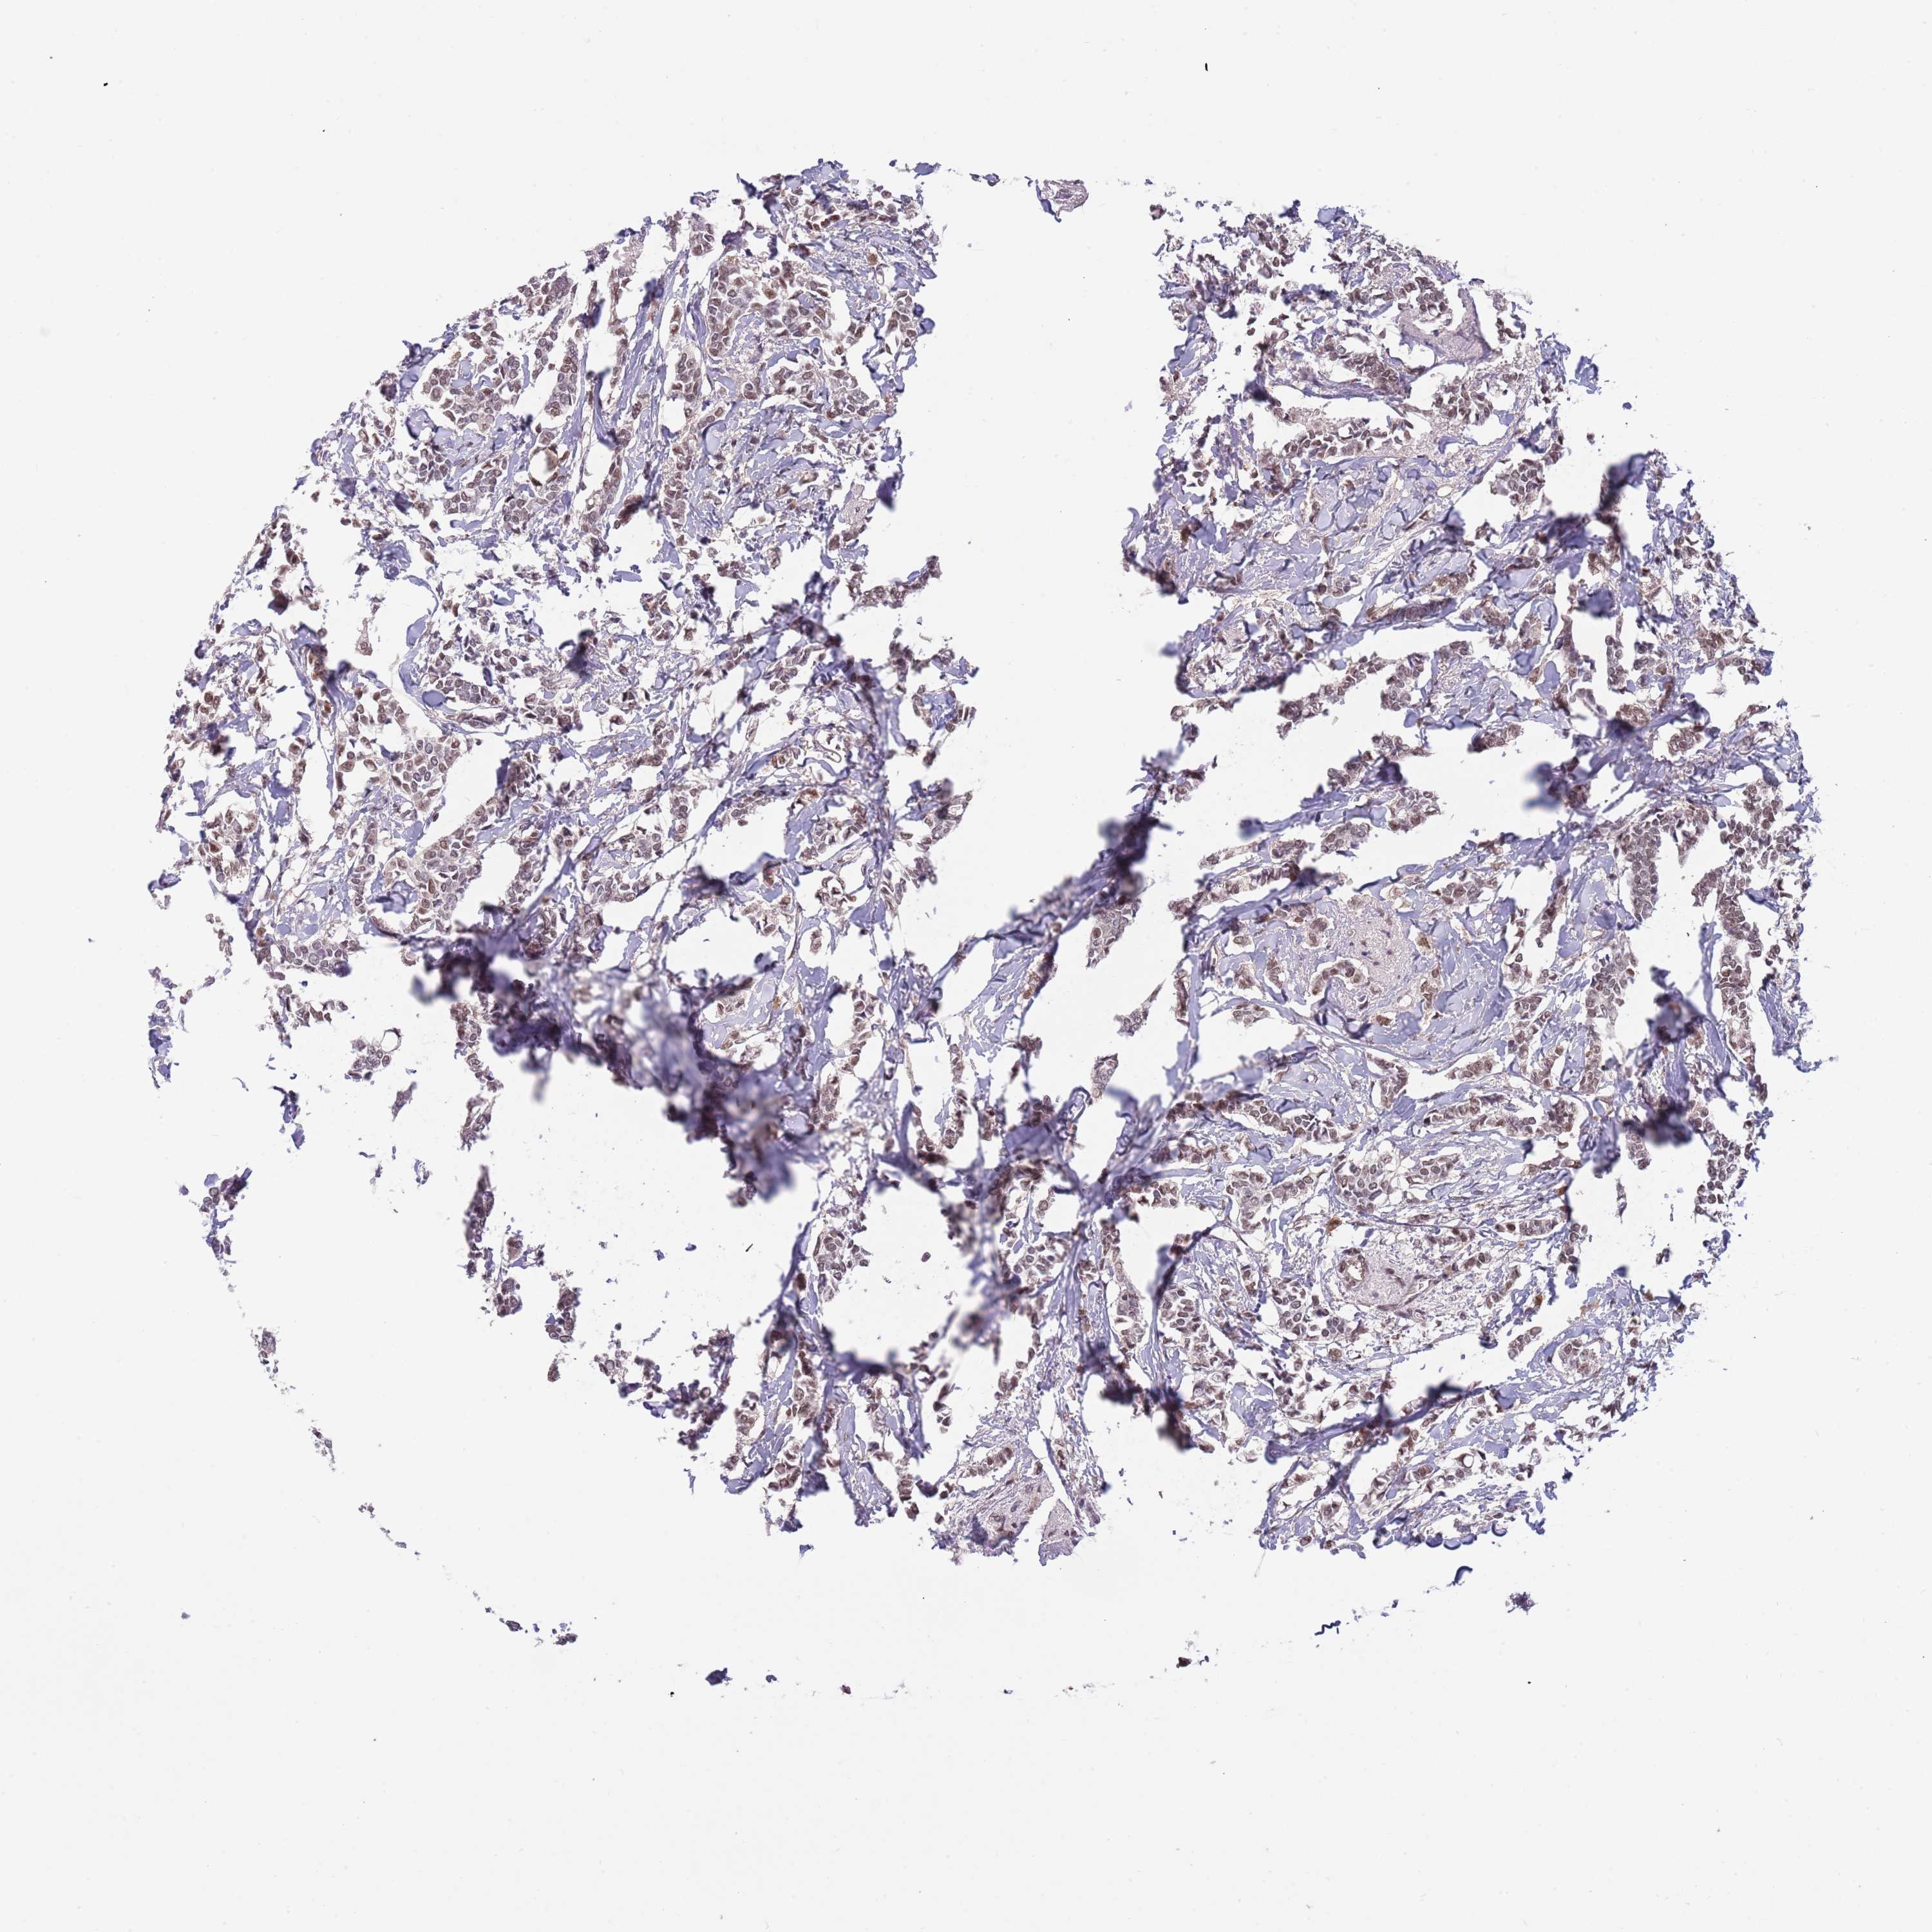

CANCER BREAST CANCER Show tissue menu

BRCA TCGA BRCA VALIDATION PROTEIN EXPRESSION